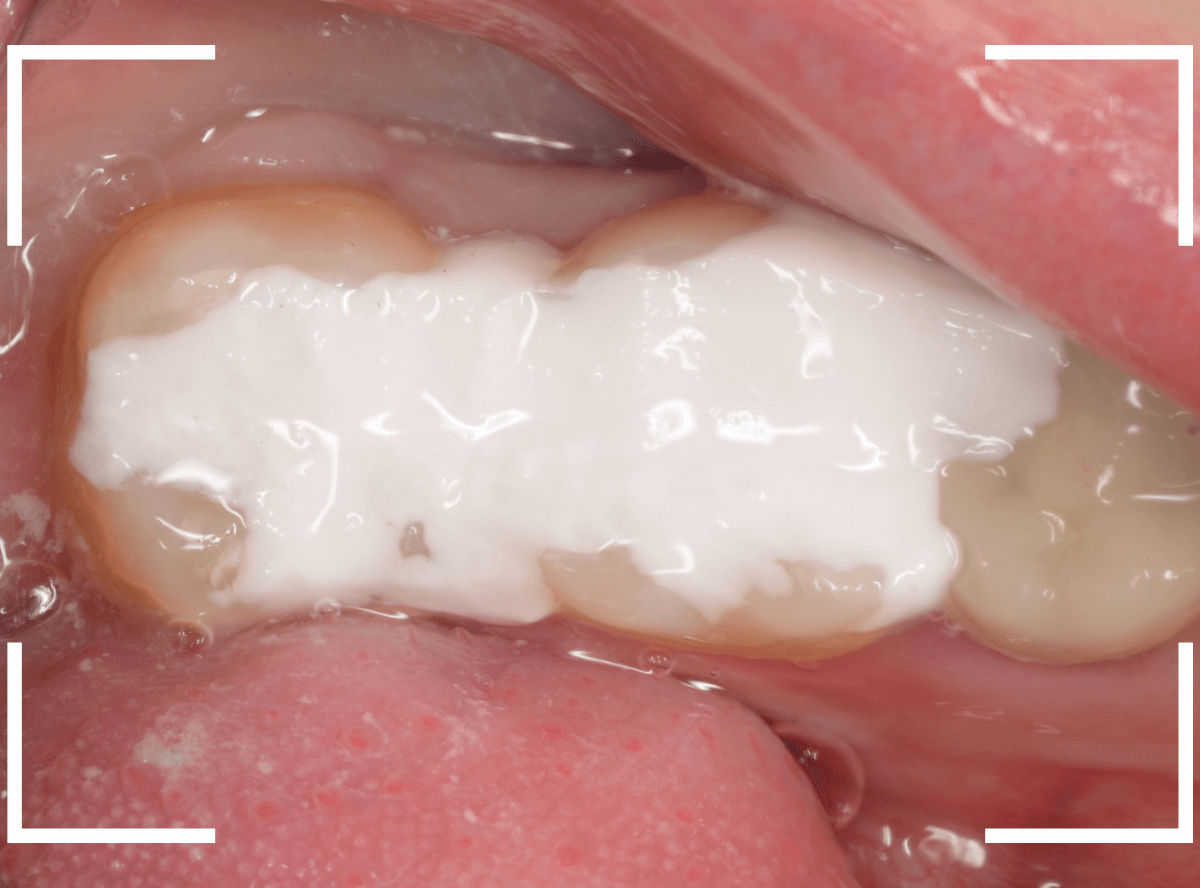

エキスカベーターを使ってほぼ全ての虫歯を除去したところです。

幸い、神経寸前で虫歯はとどまっていましたが、お薬を詰めて、しばらく経過観察します。